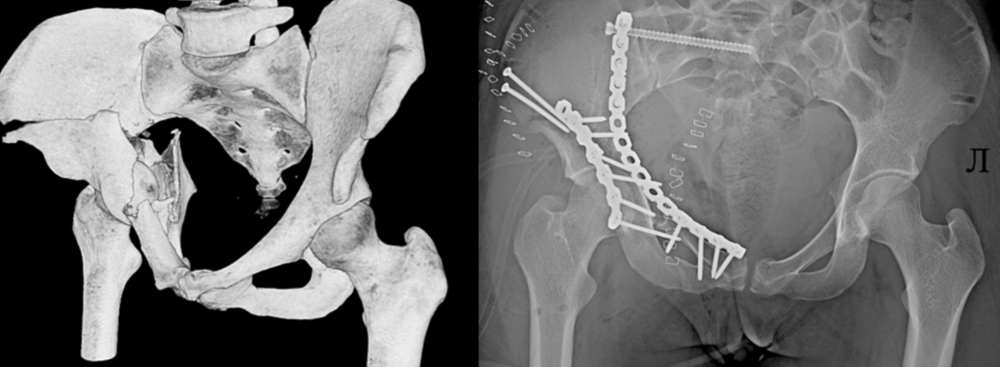

«В 14 травматологическое отделение больницы поступила 25-летняя пациентка - пострадавшая при катании на «неофициальном» спуске врезалась в бетонный блок. Диагностированы были множественные переломы костей таза. Итог - реанимационное отделение, а после стабилизации состояния – повторная 5-часовая операция: многочисленные переломы были установлены в правильном положении и фиксированы металлоконструкциями», — рассказали в больнице имени Соловьёва.